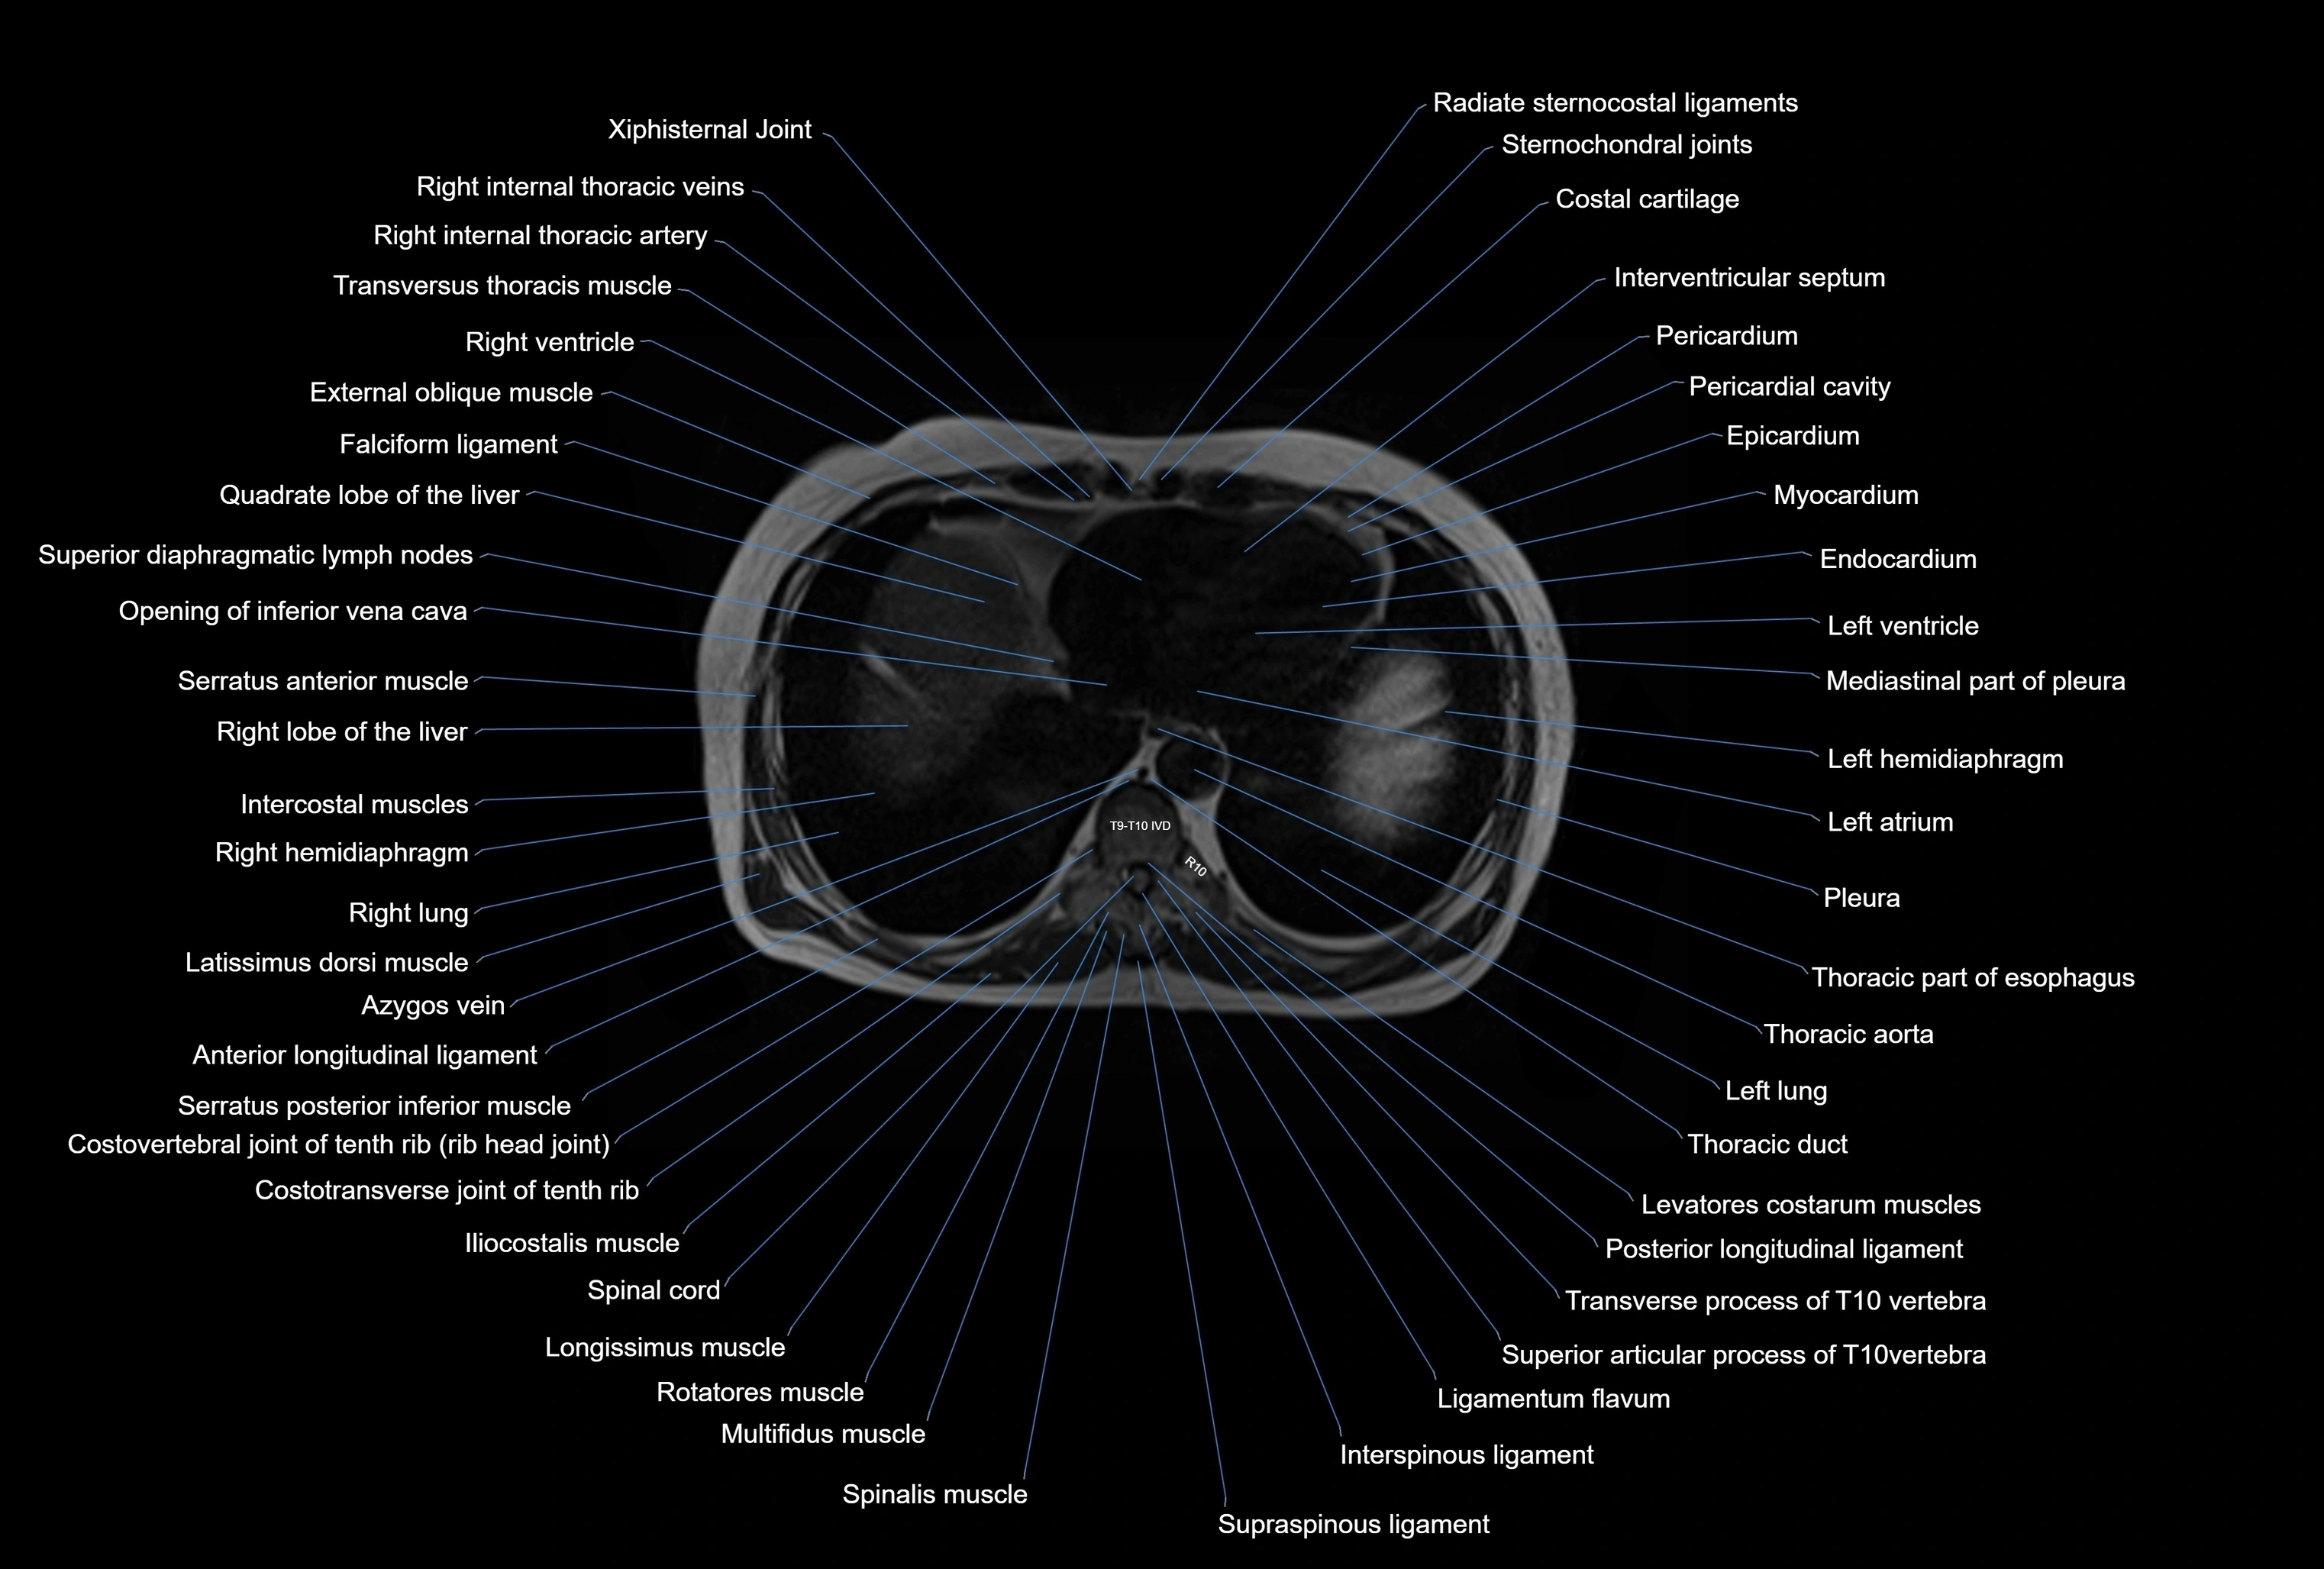

MRI images